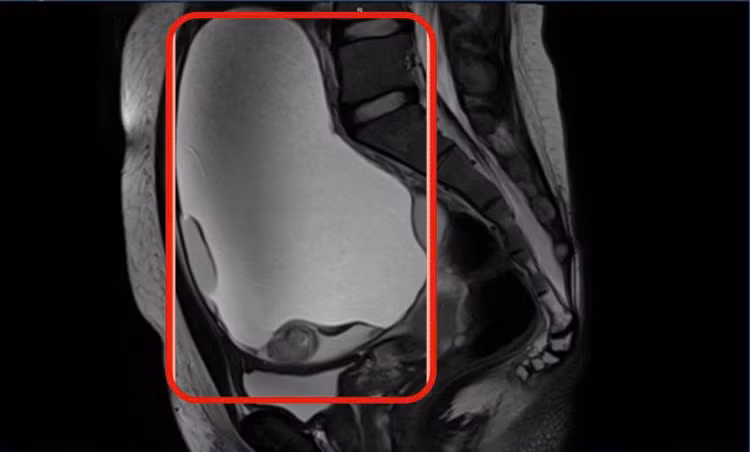

U buồng trứng 2 bên choán chỗ - Ảnh BVCC

Kết quả MRI cho thấy tử cung không bất thường, tuy nhiên hai buồng trứng đều có khối u choán chỗ. Khối u buồng trứng phải kích thước khoảng 13×15 cm, khối bên trái 8×10 cm, bên trong chứa dịch, mỡ và vôi hóa, ranh giới rõ.

Cả hai khối u đều bị xoắn – một biến chứng cấp cứu nguy hiểm. Chẩn đoán xác định u bì buồng trứng hai bên xoắn.